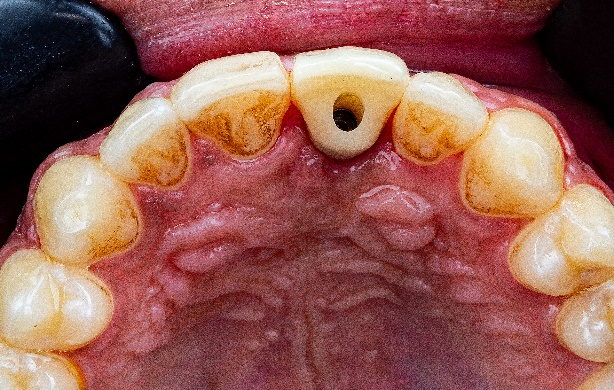

Ход лечения: Второй этап реставрации

Через шесть месяцев после операции доктор измерил толщину нарощенной кости — к этому времени она восстановилась до 5,5 мм. Остеоинтеграция имплантата прошла хорошо. Таким образом, условия для эстетической реставрации были созданы.

Рис. 13, Рис. 14: Состояние тканей перед вторым этапом имплантации: десна зажила хорошо, толщина кости достаточна.

Сканирование сканером Elite со скан-маркером проводится для определения формы временной коронки. Поскольку в данном случае устанавливается только один имплантат, нет необходимости применять фотограмметрию, чтобы определить его положение (рис. 15, рис. 16).

Примерка временной коронки показала хорошую посадку по краям и равномерное распределение точек окклюзионного контакта. Пациент одобрил форму коронки. Позже ему была установлена постоянная коронка из диоксида циркония, которая также полностью его устроила. (Рис. 21, 22, 23, 24)

Рис. 21, 22, 23, 24: результат имплантации.